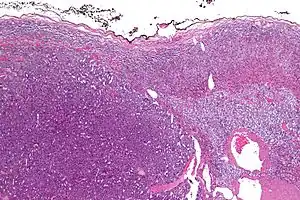

Micrograph of an adrenocortical carcinoma (left of image – dark blue) and the adrenal cortex it arose from (right-top of image – pink/light blue). Benign adrenal medulla is present (right-middle of image – gray/blue). H&E stain.